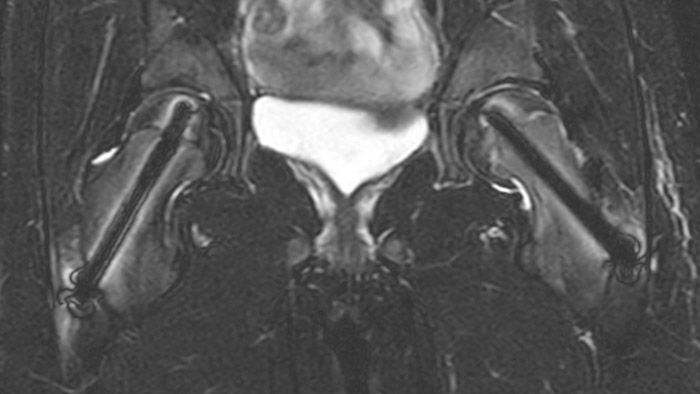

After intervention with two cannulated titan screws, it is important to check that the circumference is normal and without necrosis. The screws can cause major metal artifacts, but O-MAR allows to improve visualization of tissue and bone in the near vicinity of MR Conditional orthopedic implants1. 1 Only for use with MR Safe or MR Conditional implants by strictly following the Instructions for Use

Leukodystrophy in a teenager